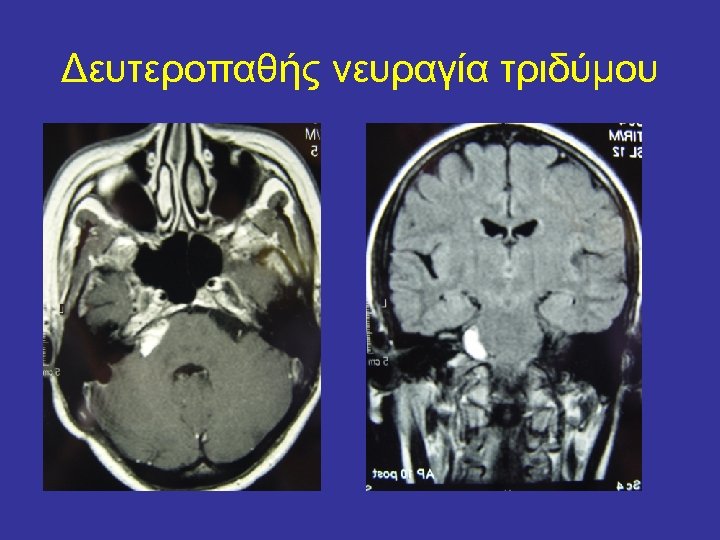

Δευτεροπαθής νευραγία τριδύμου • • Τριδυμική αυτόνομη κεφαλαλγία (TAC) Σκλήρυνση κατά πλάκας Εξεργασίες εγκεφάλου Complex regional pain syndrome Ποσοστά επιτυχίας διαδερμικών τεχνικών έως 90%. Constantoyannis C. , et al. Percutaneous balloon compression for trigeminal neuralgias and autonomic cephalalgia. Headache 2008 : 48 : 130 -34

Δευτεροπαθής νευραγία τριδύμου